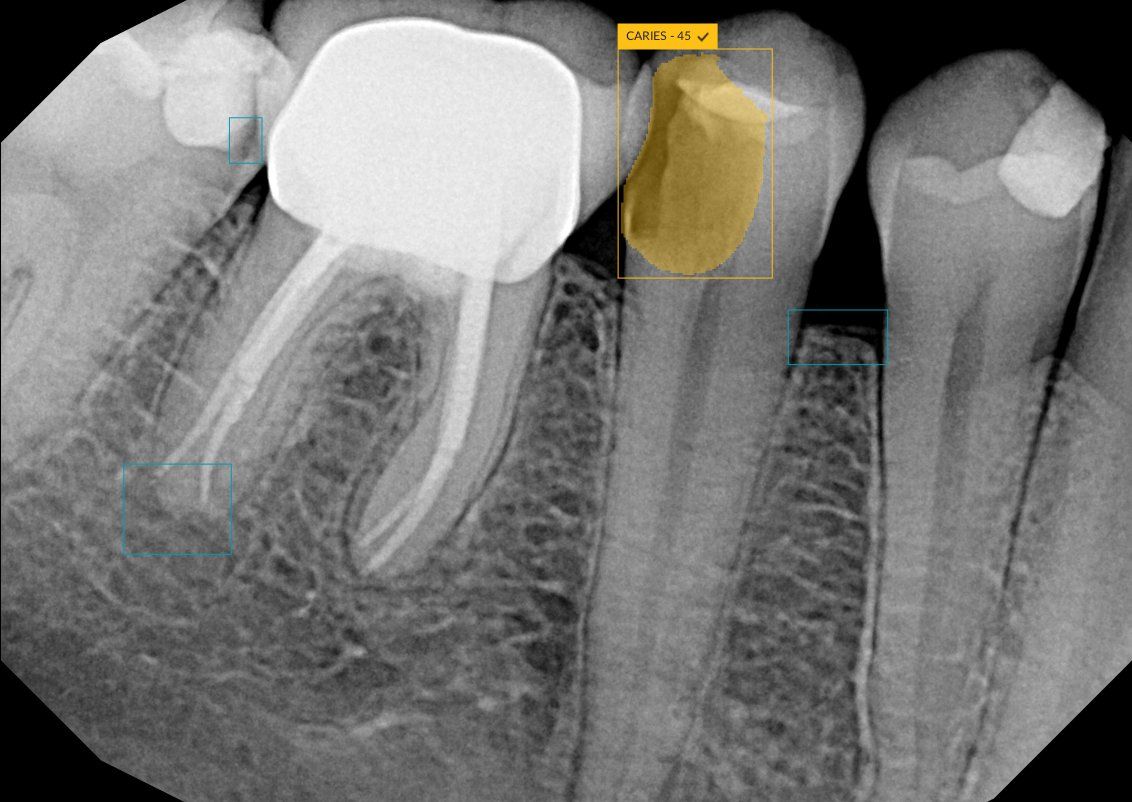

DTX Studio Clinic is designed to screen dental radiographs and annotate suspected areas of interest, allowing clinicians to make informed decisions about diagnosis and treatment. These can include 6 types of pathological dental findings: caries, discrepancy at margin, root canal defects, periapical radiolucency, bone loss, and calculus. DTX Studio Clinic allows clinicians to present patients with a more comprehensive view of their diagnosis and treatment plan, which is said to build patient understanding and increase practice efficiency.

DEXIS' new DTX Studio Clinic uses AI to highlight 6 types of pathological findings on 2D radiographs, including caries.